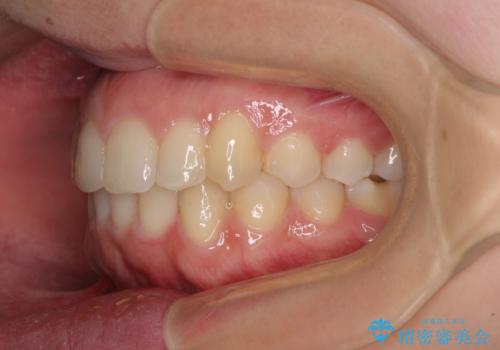

骨格的に左右にずれいている 前歯のデコボコをインビザラインで解消

- 前歯のデコボコと八重歯を気にして来院された患者様です。

叢生の程度は中等度であったため、IPR(歯と歯の間を削る)と歯列の側方拡大をメインに、インビザラインを用いて歯列を改善することとしました。

また、下顎骨の右側変位による右側臼歯の咬合を改善させるよう試みることとしました。

右側の咬合改善を目標に様々な手法を用いましたが、骨格的なズレによる不正咬合はインビザラインでは改善することができませんでした。